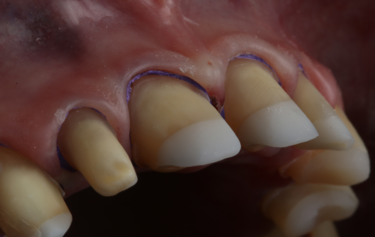

Figure 13: Gingival retraction on final preparations

Given the patient’s reduced dental arch, high strength of the final restorations would be an essential property to support the mechanics of her masticatory function. Ivoclar IPS e.max ZirCAD Prime Esthetic was chosen as the restorative material as it has a considerably higher compressive strength over IPS e.max. In addition, the shade graduation technology gives the restorations more translucency toward the incisal edges and allows them to achieve the necessary natural colouring of real teeth that’s’ so vital in an aesthetic rehabilitation[13]. Bone-sounding was completed, and there was ample sulcus depth to allow removal of approximately 1-1.5mm from the unattached gingiva, still leaving approximately 2mm sulcus depth. Using a digitally printed guide based on the provisional digital mock-up, a diode-laser was used to gentle re-contour the gingiva to give better symmetry for the planned final restorations (Fig. 10). The teeth were then prepared to respect the minimum manufacture tolerance of Zirconia restorations, whilst keeping the preparation into the natural teeth as minimal as possible following the Gürel reduction technique[14]. This technique helps safeguard that only the necessary tooth-surface is sacrificed during crown or veneer preparation, and ensures that the correct thickness of reduction for the planned restorative medium is achieved. Depth grooves of 0.8mm were cut mid-facially and 1.5mm reductions incisally, and the teeth then prepared for full coverage restorations respecting these grooves as the maximum tooth reduction level (Fig. 11).

A 6-week period was allowed to pass to give the gingiva time to heal and settle around the milled temporary restorations. On review the patient was very happy with the aesthetics of her smile but wanted the teeth a little whiter in colour. The form and function of the teeth was balanced, and the patient was comfortable at the new OVD. The temporary restorations were easily removed, followed by final refinement of the tooth preparations, and then retraction with PTFE placed into the sulcus ahead of a Trios intra-oral digital scan of the final preparations (Fig. 13). The posterior bite relationship of the prepared teeth was digitally recorded over the premolar area by using the anterior upper and lower 4 crowns to support the patient in the correct centric relation position.